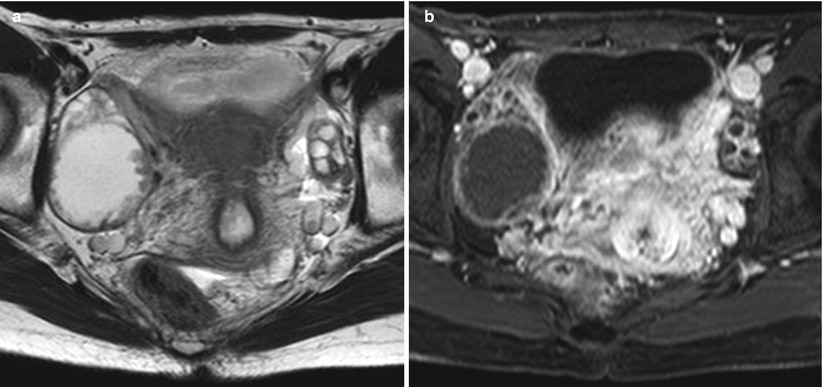

a Picture of an ovarian seromucinous borderline tumour. The

a Picture of an ovarian seromucinous borderline tumour. The capsule is

Tomographic and Magnetic Resonance Imaging of Borderline and Serous Tumors